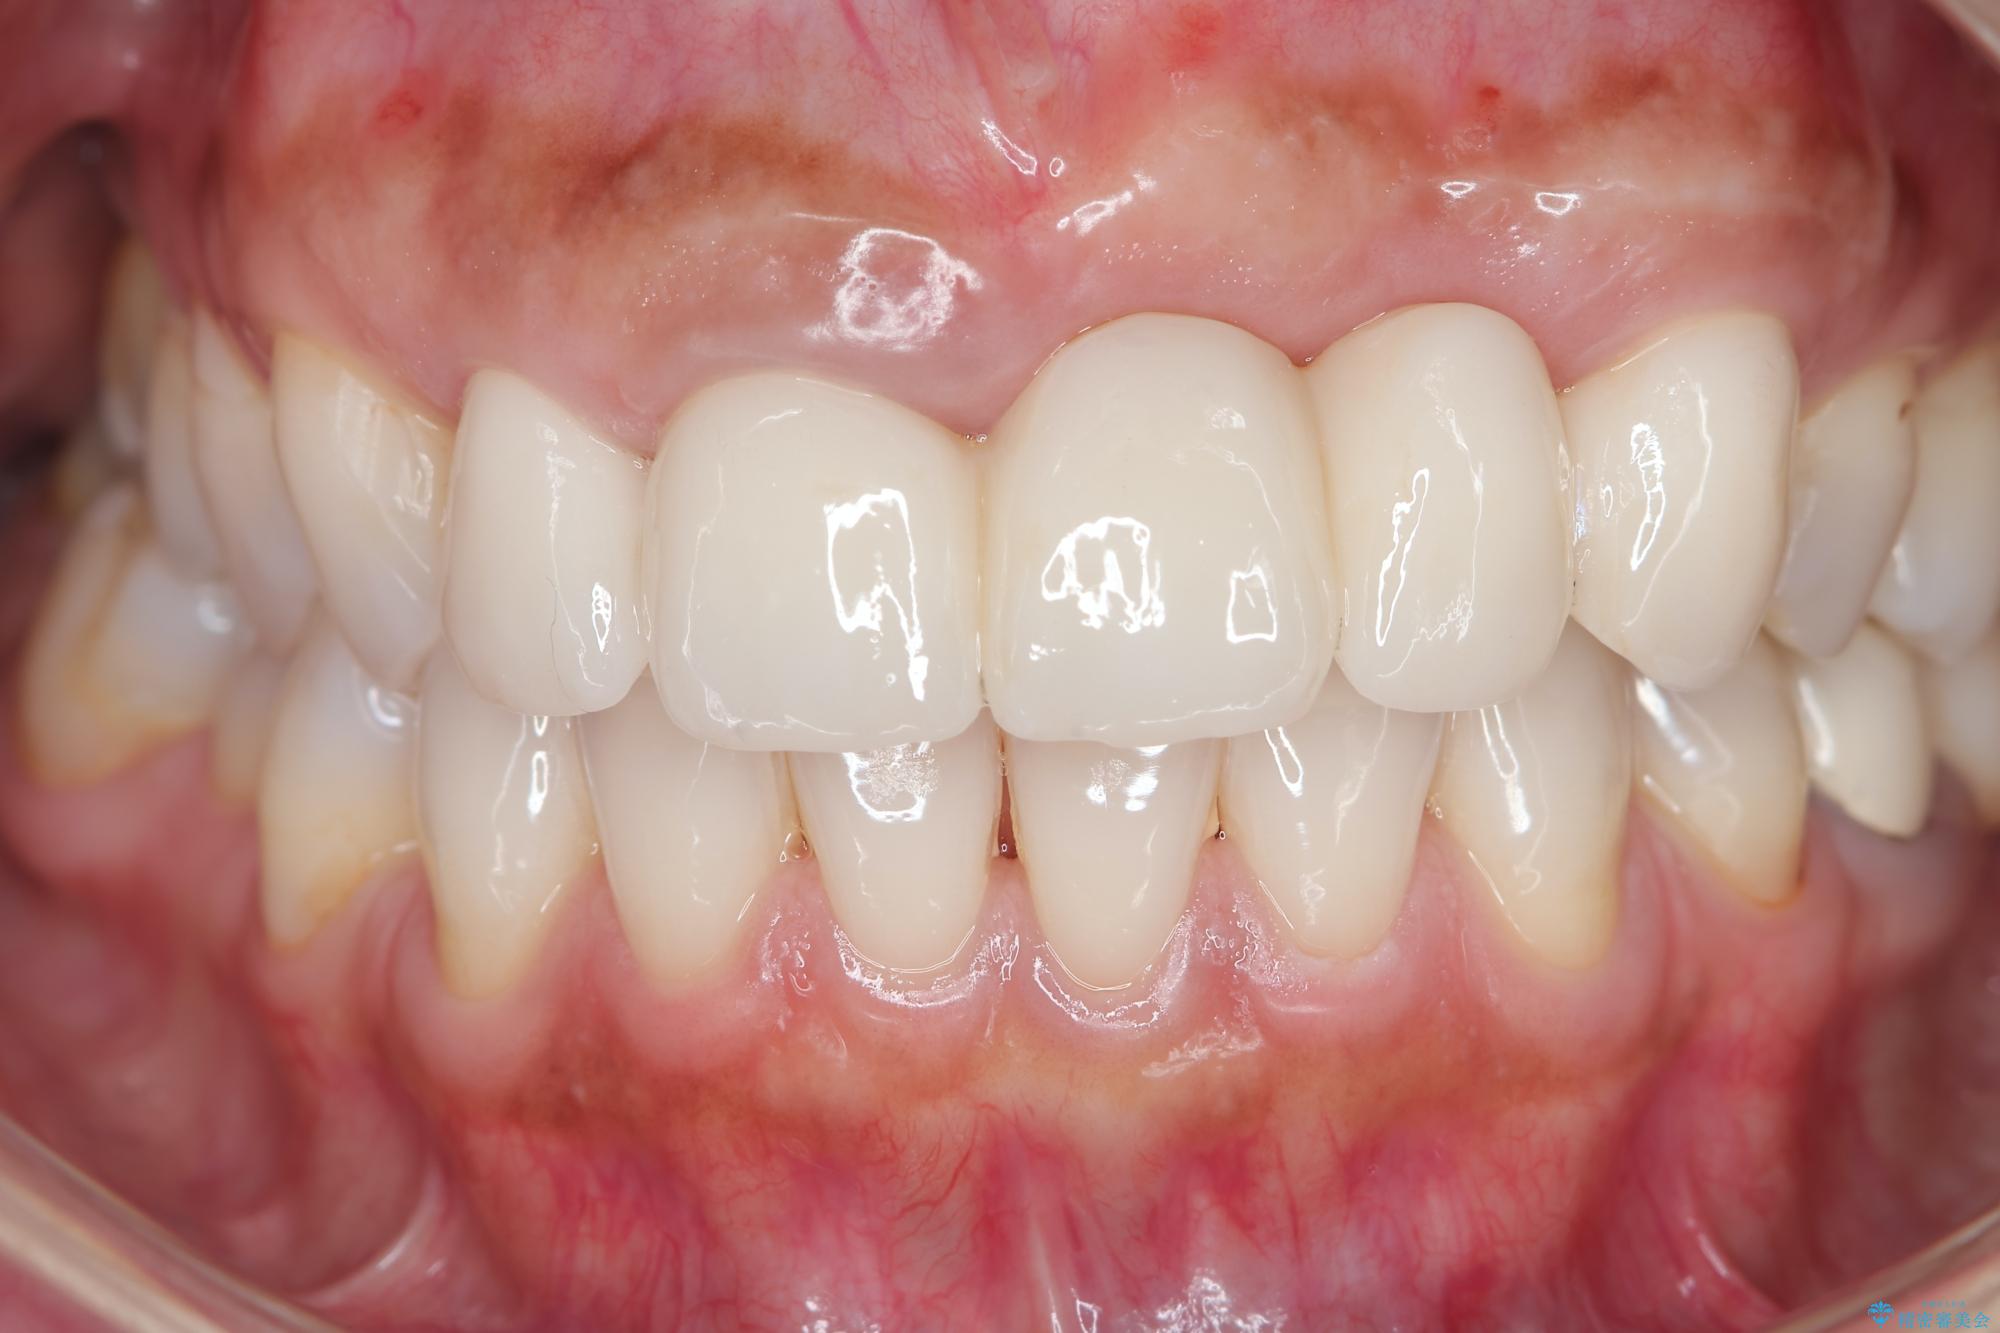

治療を終えて

一件綺麗に見えるセラミックも適合や精度が悪いと、内部で虫歯が進行し亀裂や破折、悪臭の原因となることがあります。

治療後

歯槽堤保存術を併用したブリッジ治療 治療後画像 歯槽堤保存術を併用したブリッジ治療 治療後画像 歯槽堤保存術を併用したブリッジ治療 治療後画像 歯槽堤保存術を併用したブリッジ治療 治療後画像 歯槽堤保存術を併用したブリッジ治療 治療後画像 歯槽堤保存術を併用したブリッジ治療 治療後画像 歯槽堤保存術を併用したブリッジ治療 治療後画像